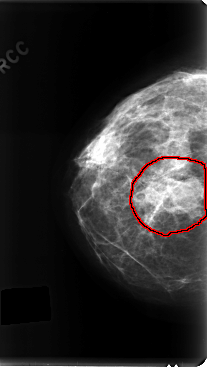

C_0197_1.RIGHT_MLO

FILE: C_0197_1.RIGHT_MLO.OVERLAY

TOTAL_ABNORMALITIES 1

ABNORMALITY 1

LESION_TYPE MASS SHAPE LOBULATED MARGINS ILL_DEFINED

ASSESSMENT 4

SUBTLETY 5

PATHOLOGY MALIGNANT

TOTAL_OUTLINES 1

BOUNDARY